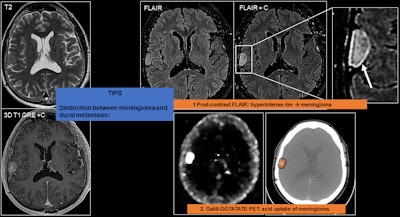

Diffuse dural thickening and enhancement may occur, and it can appear smooth or nodular. Focal dural mass mimicking meningioma may be seen, and in these cases, it is not easy to differentiate between the two entities on conventional MRI, they added.

On PET imaging with gallium-68 DOTATATE, meningiomas usually show high uptake because they contain somatostatin receptors. “However, caution is advised, as metastases from neuroendocrine tumors also show high uptake. Meningiomas are typically characterized by a complete ring or > 50% enhancement on the postcontrast FLAIR sequence (‘CE-FLAIR rim sign’),” the Madrid researchers pointed out.

The main differential diagnosis of focal dural metastasis is a meningioma, which is much more common, and they are difficult to differentiate on conventional MRI. To help differentiate them, postcontrast fluid attenuated inversion recovery (FLAIR) sequences can be used. Meningiomas may show up as a hyperintense rim on FLAIR MRI and Ga-68 DOTATATE PET, as meningiomas show intense uptake due to the presence of somastotatin receptors.